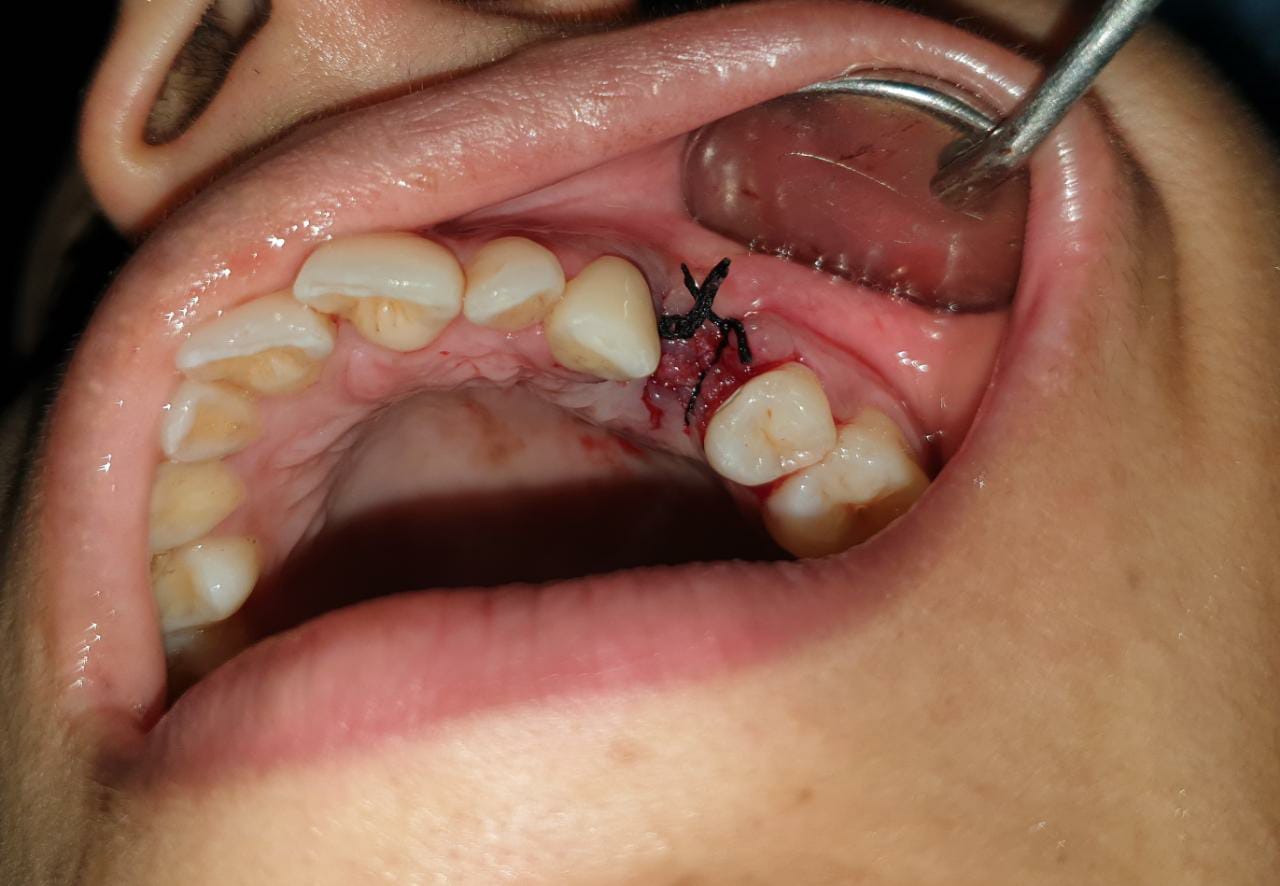

2.4 Live Surgical Demo Of Implant Placement

2.5 Implant Placement

2.6 Implant Placement

2.7 Implant Placement

2.8 Implant Placement

2.9 Implant Placement